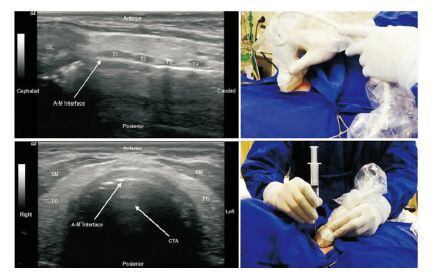

1.4.2 超声辅助组(ultrasound group)定位下经皮扩张气管切开术采用Portex经皮气管切开导管套件进行操作,患者仰卧位,肩背部垫高,颈过伸,头取正中位,头后仰,暴露气管,常规消毒铺巾、退出气管插管距门齿17~18 cm,超声定位第1、2气管环,观察穿刺部位是否存在血流频谱,利多卡因局部浸润麻醉后,沿局麻点横向切开颈前皮肤,切口约1.5~2.0 cm,套管针在切口中点穿刺进入气管内抽回到气泡后,拔出针芯,放入导丝,拔出套管针,沿导丝置入气切套管,立即给予纤维支气管镜确认气切套管位置后拔出气管插管,气囊充气后准备接呼吸机并固定套管。见图 1。

| 图 1 超声辅助定位下经皮扩张气管切开图示 |